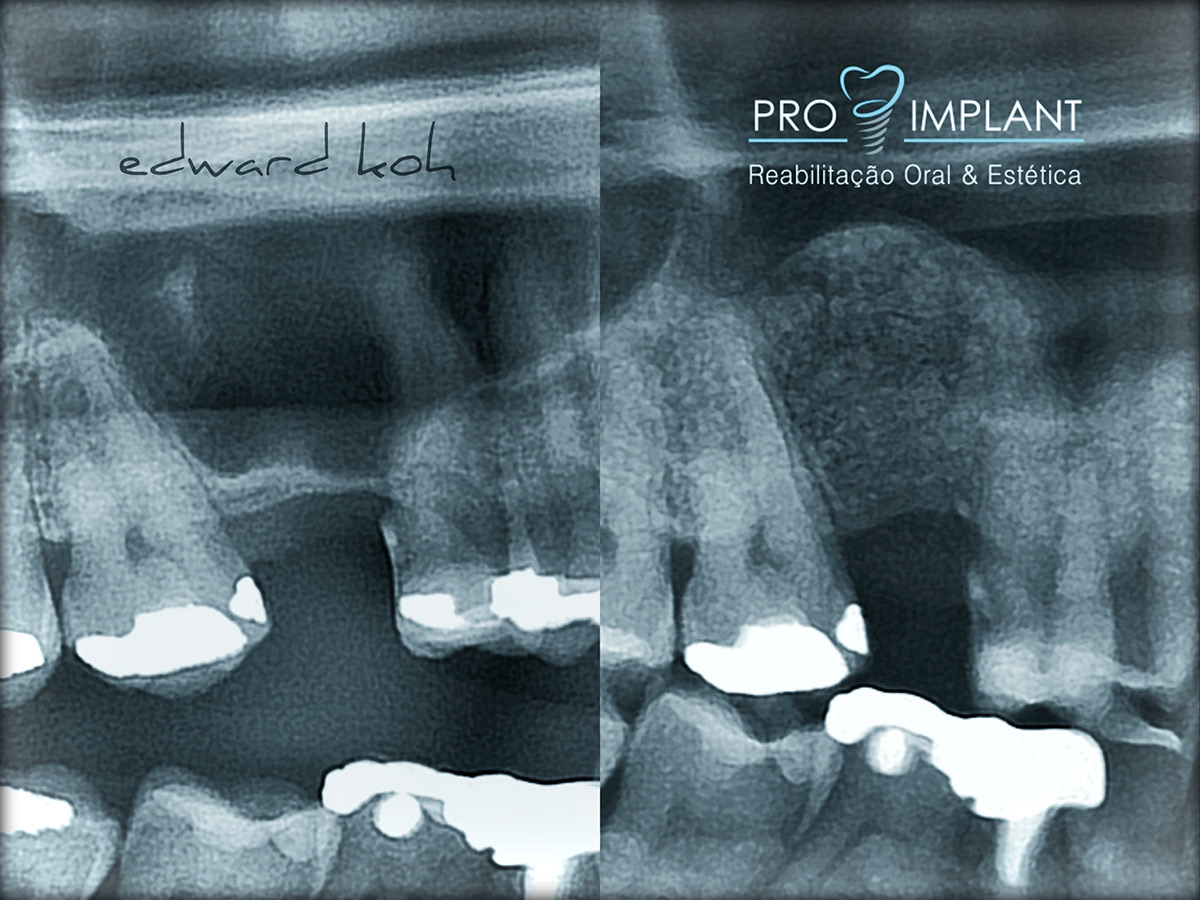

A perda de dentes pode levar a problemas estéticos, de oclusão (mordida) e perda óssea. Portanto é fundamental uma rápida reposição do elemento perdido. Os Implantes Dentários são parafusos de titânio que substituem a raiz dos dentes perdidos. O implante dental serve de apoio para a prótese (coroa) que deve ser semelhante aos dentes: naturais em estética e função. Os Implantes Dentários podem ser indicados para repor a perda de todos os dentes, de alguns ou de apenas um dente.

O Implante Dentário inibe a atrofia do osso após a perda de um dente; é fixo e não há necessidade de comprometer os dentes naturais adjacentes.